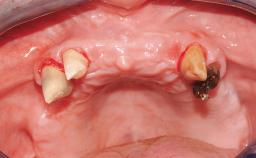

Immediate Loading of Six Implants in the Mandible and Six Implants in the Maxilla and Final Restoration with Full-Arch CAD/CAM Metal Framework FDPs Involving Digital Planning and Guided Surgery

Ali Tahmaseb, Renaat De Clerck, Daniel Wismeijer

Immediate loading of dental implants is increasingly popular with clinicians and patients. The idea of delivering a restoration directly after implant insertion,combined with a less invasive procedure (flapless protocol), has made treatment protocols involving dental implants more accessible to dentists and patients. However,immediate-loading concepts require sophisticated and exact planning. To facilitate this, conventional panoramic tomographs and periapical radiographs are often taken with the patient wearing a radiographic template simulating the preoperative prosthetic design. However, these radiographs do not provide all the necessary information. In addition, some protocols call for conventional surgical templates fabricated on the diagnostic cast. These will inform the bone drilling points and drill angles, but do not reference the underlying anatomical structures or provide exact 3-D guidance.

Case Type Edentulous Maxilla